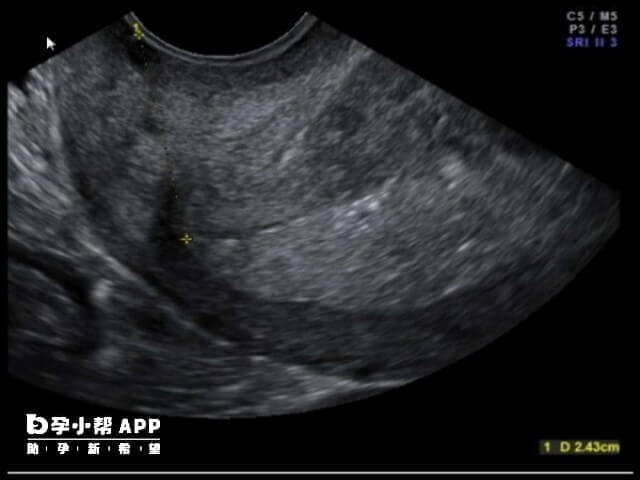

3、浆膜下子宫肌瘤在超声下可以看到突向宫腔外的子宫肌瘤,试管移植是将胚胎移植到女性子宫,即对于试管移植是没有什么影响的,所以是可以进行移植手术的。